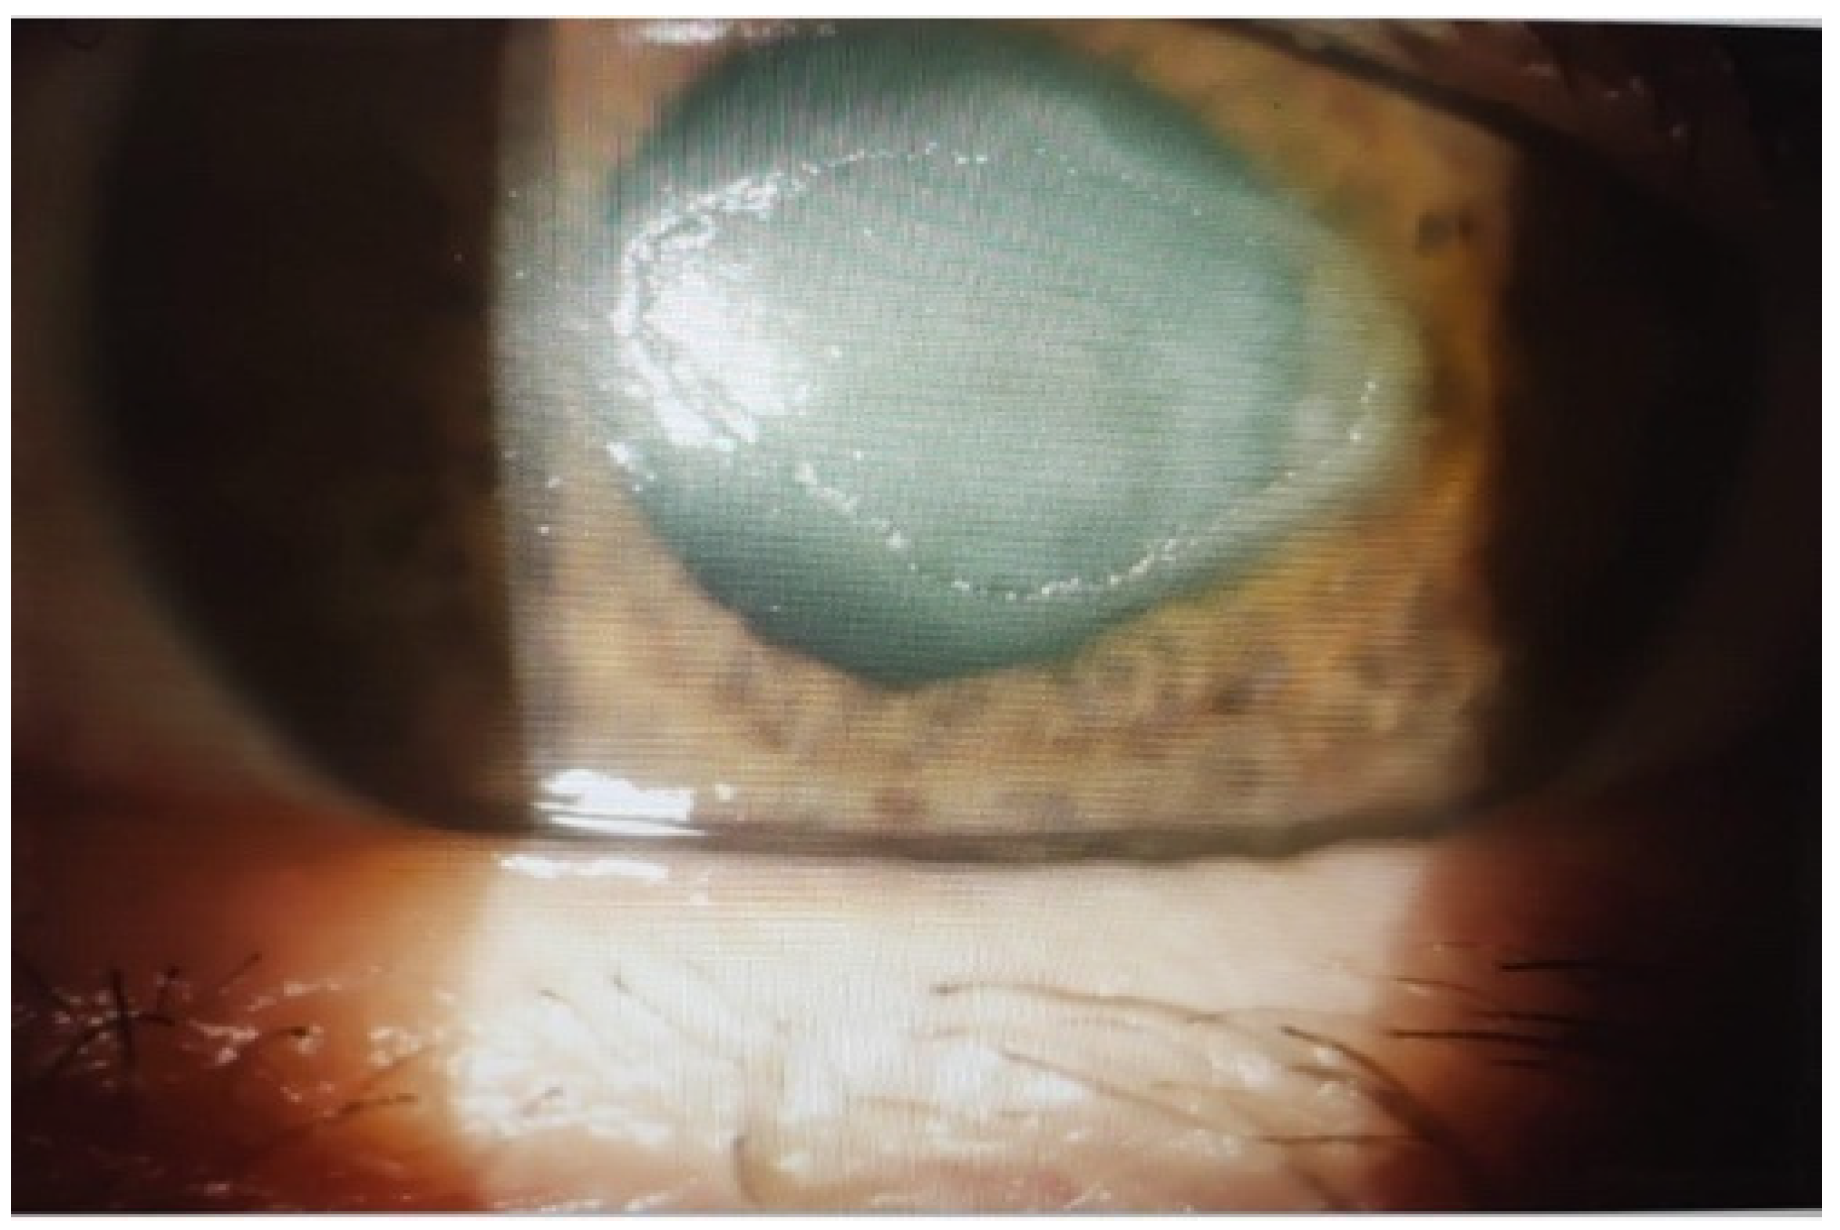

2.4. Outcomes in Group III: Neurotrophic Corneal Ulcers

- Group III (n = 10): neurotrophic corneal ulcers.

| III—Neurotrophic corneal ulcers | 10 | Corneal ulcers due to loss of corneal innervation | Poor healing response due to reduced corneal sensitivity, with high risk of perforation and irreversible visual loss. |